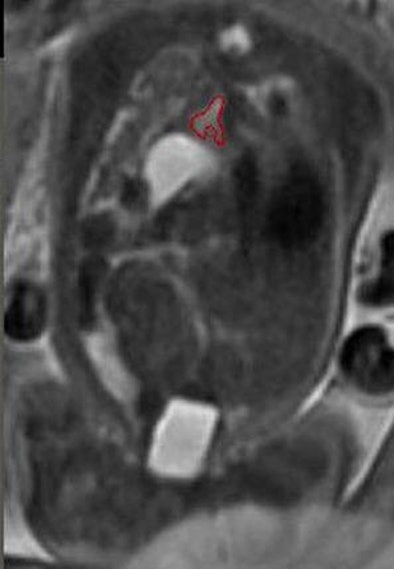

| Above, MRI of left lung (outlined in red) in CDH patient. Below, 3D reconstruction of normal lungs by fetal MRI. All images courtesy of Timothy Lee, MD. |